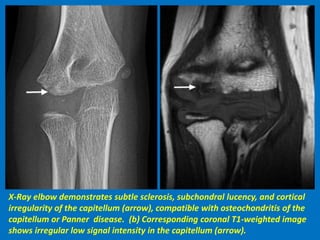

X-Ray elbow demonstrates subtle sclerosis, subchondral lucency, and cortical

irregularity of the capitellum (arrow), compatible with osteochondritis of the

capitellum or Panner disease. (b) Corresponding coronal T1-weighted image

shows irregular low signal intensity in the capitellum (arrow).

X-Ray elbow demonstratessubtle sclerosis, subchondral lucency, and cortical irregularity of the capitellum (arrow), compatible with osteochondritis of the capitellum or Panner disease. (b) Corresponding coronal T1-weighted image shows irregular low signal intensity in the capitellum (arrow).